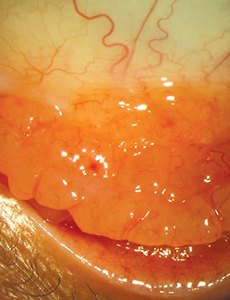

아스퍼질러스증, 안와의 아스페르길루스증, Orbial Aspergillosis 의 진단과 치료 아스퍼질러스(Aspergillosis)는 면역기능이 저하되지 않은 정상인에서는 드물게, 면역저하자에서는 다소 흔하게 발견되는 곰팡이, 진균입니다. 안와 아스퍼질러스증(Orbital aspergillosis)은 비교적 드문 질환이나 최근들어 항생제, 스테로이드제, 항암제의 빈번한 사용으로 인하여 점차 증가하는 추세를 보이고 있습니다. 주로 부비동에서 감염이 파급되어 발생하며 심한 경우 안와나 두개강 내까지 전파되기도 하며 항암제 사용이나 후천성면역결핍증 등으로 인해 저항력이 감퇴된 환자에서 주로 발생합니다. 진단은 임상양상이나 단순 방사선 소견에만 의존할 수 없고 조직생검을 하여 병리조직학적 검사를 반드시 시행해야 합니다. 격벽과 분지된 균사가 약 45° 각도로 배열되어 형성된 균사가 발견되어야 하는데, .. 2018. 8. 24.